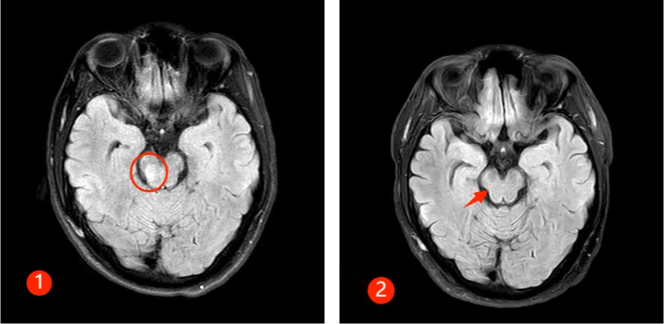

半年前,30来岁的谭先生突然出现颈肩部疼痛不适及肢体麻木,此后短短数天迅速出现四肢瘫痪及大小便失禁,生活不能自理。正值风华正茂的年纪,谭先生一时无法接受,心急如焚的父母带着吓坏了的谭先生来郑州大学第五附属医院就诊,入住神经内科二病区。入科时患者已四肢全瘫,紧急完善相关检查,发现患者脑干、颈髓、胸髓、腰髓广泛病变(见图①),随后完善腰穿及相关抗体检查,最终确诊为MOGAD。

经过及时的免疫治疗,患者病情逐渐好转,出院时患者已能下床行走,再次拾起对生活的信心,复查磁共振,患者脑干、颈髓、胸髓、腰髓的病变已明显好转(见下图②)。半年后随访,患者已恢复正常的生活,预后非常好。